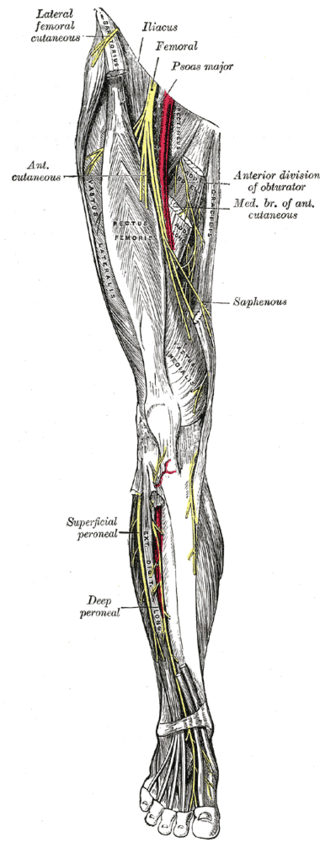

앞무릎 전체 통증: 대퇴신경포착(Femoral nerve entrapment)

아픈 부위를 가르켜 보라고 하면 정확한 부위를 가르키지 못하고 전체가 다 아프다고 하시는 분들이 있습니다. 임상 경험상 이런 경우는 대퇴신경의 포착이거나 중추신경의 과민화로 인한 요추 2,3,4번 레벨의 연관통으로 보여집니다.

처음 시작은 무릎 통증이었으나 오랜 시간 낫지 않고 반복적인 무리를 하면 전체적으로 다 아프다고 느끼게 됩니다. 이런 경우 대퇴신경의 척추레벨인 요추2,3,4번 다열근의 압통점을 확인하여 먼저 치료하게 됩니다. 그러면 최초 시작한 부위의 통증으로만 남게 되는 경우가 많죠. 또는 대요근에 의해 대퇴신경이 포착될 수 있습니다. 대퇴신경이 지배하는 대퇴사두근의 허혈성 통증이 나타나고 무릎 전체적으로 통증을 느끼게 됩니다.